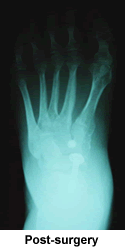

Hello, my name is Sandra Traver and I live in Millville, Pa. When I was born, I was born with dislocated hips. When I was 50 years old, I had two hips replaced, nine days apart. After the second hip replacement, I ended up with nerve damage and a drop foot on the left foot. I was told by the doctor that it could be fixed, that's when I met Doctor Kenneth Leavitt. He checked me out and found that I have Charcot Marie Tooth Disease (CMT), which is a nerve disease. He said he could have me up and walking like before surgery. He fused my foot bones together and did a nerve transplant and put a rod in my foot to be removed after 12 weeks of bed rest.